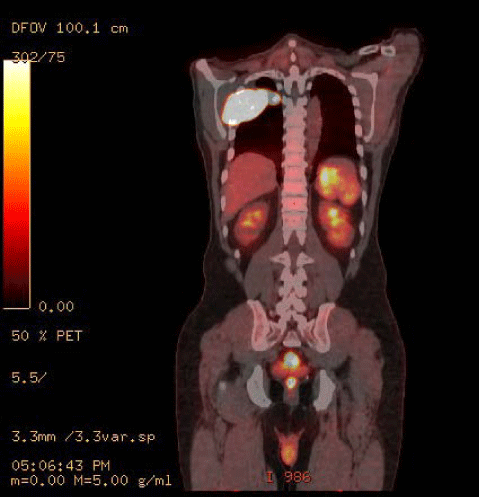

Figure 1: PET/CT prior to chemotherapy: Hypermetabolic postero-lateral right chest wall lesion with a maximal standardized uptake value (SUV). Multiple enlarged hypermetabolic nodules scattered throughout the mesentery, retroperitoneum, left inguinal region, and spleen.